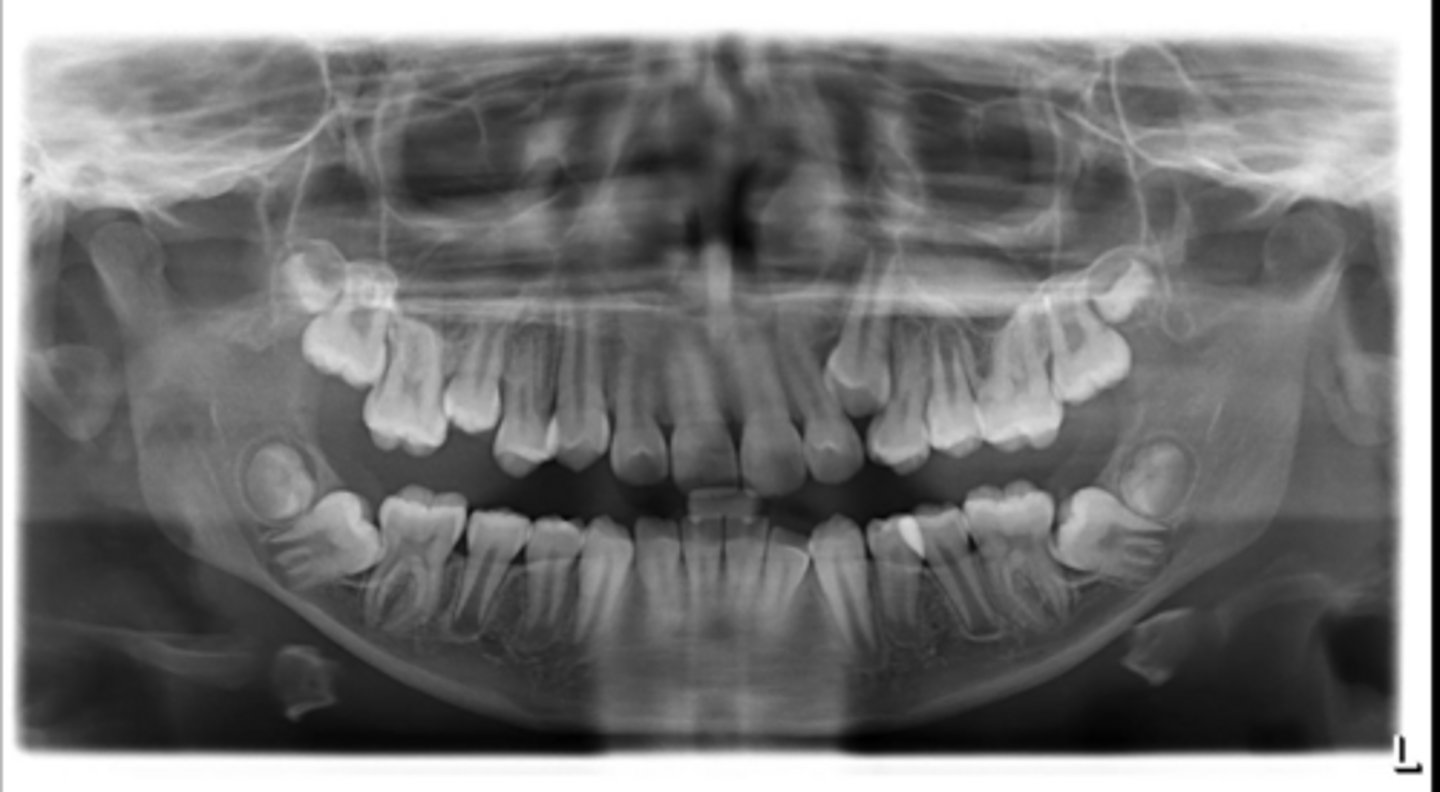

Right primary canine

Are there retained primary teeth?

Yes

Are there any impacted teeth?

Are the condyles symmetrical?

Is there a dilacerated root?

No

The mandibular left side has normal premolar/canine eruption, but the rigth side is abnormal.

Is the eruption pattern of this patient normal or not?

Are there any supernumerary teeth?

Are there any retained primary teeth?

Not at this stage

Are there impacted teeth?

Yes, within the range of normal

Symmetric condyles?

Yes - maxillary first molar

Dilacerated roots?

Yes - laterals

Are there congentially missing teeth in the maxillary arch?

Yes - an incisor

Are there congenitally missing teeth in the mandibular arch?

Yes - upper right near the premolar

Any impacted teeth?

Can't see, so can't say

Yes - #2, also #27?